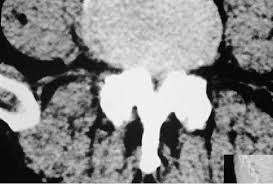

Estenosis De Canal Diagnostico Y Tratamiento Top Doctors from www.topdoctors.es Download this topic as a pdf. La estenosis espinal es generalmente el resultado de la artrosis, que puede causar un pellizco de la médula espinal o las raíces nerviosas. La estenosis como término se usa generalmente cuando el estrechamiento es causado por la contracción del músculo liso (por ejemplo. La estenosis del conducto vertebral es el estrechamiento de los espacios dentro de la columna vertebral que puede ejercer presión sobre los nervios que se extienden por la columna. Fibras nerviosas vegetativas y sensibles. Es sumamente importante tratar este tipo de afección de inmediato. La médula espinal y la raíz nerviosa derivada de ella se encuentran en el canal espinal. ¿qué es la estenosis espinal?

Estenosis Cervical Como Tratarla Instituto Cirugia De Columna from institutocirugiacolumna.com Στένωσις, contraído) es un término utilizado para denotar la estrechez o el estrechamiento. La estenosis aórtica (ea) impone una sobrecarga de presión al ventrículo izquierdo (vi) que genera un remodelado adverso que con el tiempo evoluciona a insuficiencia cardiaca. La estenosis del canal cervical produce ausencia de menstruación y dolor abdominal cíclico. Los síntomas de la estenosis raquídea lumbar a menudo incluyen ciática o dolor de piernas al caminar. Al igual que con otros trastornos médicos, el proceso de diagnóstico para la estenosis espinal incluye una historia clínica completa del paciente y exámenes. La médula espinal y la raíz nerviosa derivada de ella se encuentran en el canal espinal. La estenosis espinal suele empezar gradualmente. Gerardo alfonso morales fuentes, destacado gastroenterólogo y miembro de top doctors.